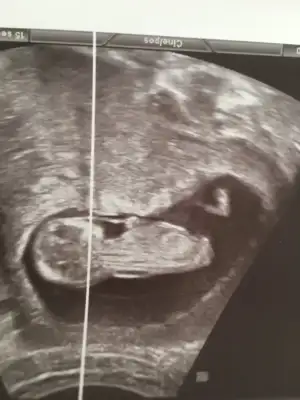

Şu şekle göre kız mı acaba dedim ama 🙈 ben de çok anlayamıyorum ☺️

• EFA1A1E3-9F6C-4CDF-BE1C-54E1D5F171DD.webp

EFA1A1E3-9F6C-4CDF-BE1C-54E1D5F171DD.webp

23,1 KB · Görüntüleme: 92